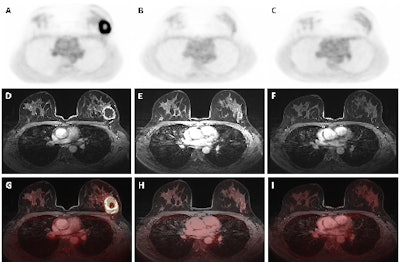

Dedicated breast F-18 FDG PET/MRI exam pre- (A, D, G), mid- (B, E, H), and post-NAC (C, F, I) of a 41-year-old patient diagnosed with a triple negative (TN), grade 2, invasive carcinoma. The SUVmax values of the primary tumor were 14.68 pre-NAC, 1.69 mid-NAC, and 1.87 post-NAC, while SER values were 1.19, 0.52, and 0.63, respectively. Figure courtesy of Melissa Lenaerts, PhD, Dr. Thiemo van Nijnatten, PhD, et al and presented at EUSOBI 2025.

Univariable Cox regression showed no significant association between pre- and mid-NAC PET- and MRI-derived parameters and EFS, the researchers said. Post-NAC, they found a significantly (p < 0.1) positive association with recurrence and/or death for the maximum standardized uptake value (SUVmax; hazard ratio [HR] 1.41 [90% confidence interval [CI] 1.089-1.831], p = 0.029), SUVpeak (HR 1.79 [90% CI 1.138-2.828], p = 0.035), SUVmean (HR 1.8 [90% CI 1.110–2.930], p = 0.046), tumour size (HR 1.04 [90% CI 1.002-1.082], p = 0.087), and signal enhancement ratio (SER; HR 6.46 [90% CI 1.111-37.511], p = 0.081) of the primary tumor.

“For mid-NAC and post-NAC, patients with SUVmax above the median value tend to have higher risk of recurrence and/or death compared to patients with lower SUV value,” they noted. “Regarding post-NAC SER, patients with a value above the median also tend to have a poorer EFS compared to patients with lower SER values. However, none of the observed differences were statistically significant.”